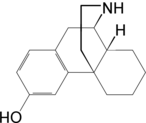

Morphinans

Morphinan series

- 3-Hydroxymorphinan

Structures

| Other morphinans | ||||

|---|---|---|---|---|

4-chlorophenylpyridomorphinan 4-chlorophenylpyridomorphinan |

Cyclorphan Cyclorphan |

Dextrallorphan Dextrallorphan |

Levargorphan Levargorphan |

Levophenacylmorphan Levophenacylmorphan |

Levomethorphan Levomethorphan |

Norlevorphanol Norlevorphanol |

N-Methylmorphinan N-Methylmorphinan |

Oxilorphan Oxilorphan |

Phenomorphan Phenomorphan |

Dextromethorphan Dextromethorphan  levomethorphan levomethorphan |

Morphanol Morphanol |

Ro4-1539 Ro4-1539 |

Stephodeline Stephodeline |

Xorphanol Xorphanol |